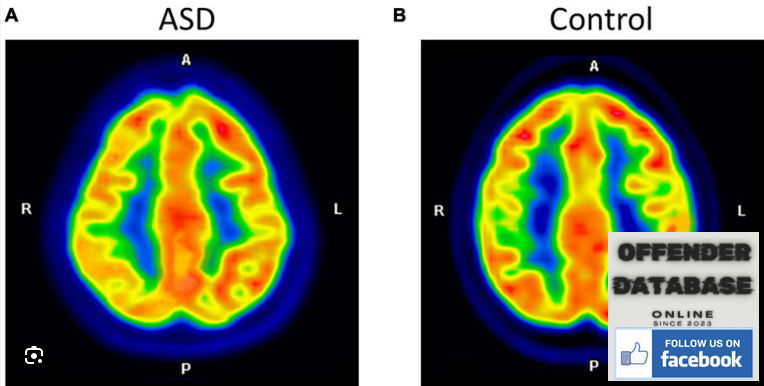

Functional Brain Differences in ASD

1. Differences in the Default Mode Network (DMN)

- The DMN (responsible for self-reflection and social thinking) is less active in ASD.

- This may explain why social interactions feel less intuitive for autistic individuals.

πΉ Findings: fMRI scans showed reduced DMN activity in ASD, making social cognition more effortful.

2. Hyperconnectivity in Sensory Areas

- Autistic brains often have increased connectivity in sensory processing areas (vision, sound, touch).

- This can explain sensory sensitivities commonly reported in ASD.

πΉ Findings: ASD individuals had excessive connectivity in sensory regions, leading to heightened sensory perception.